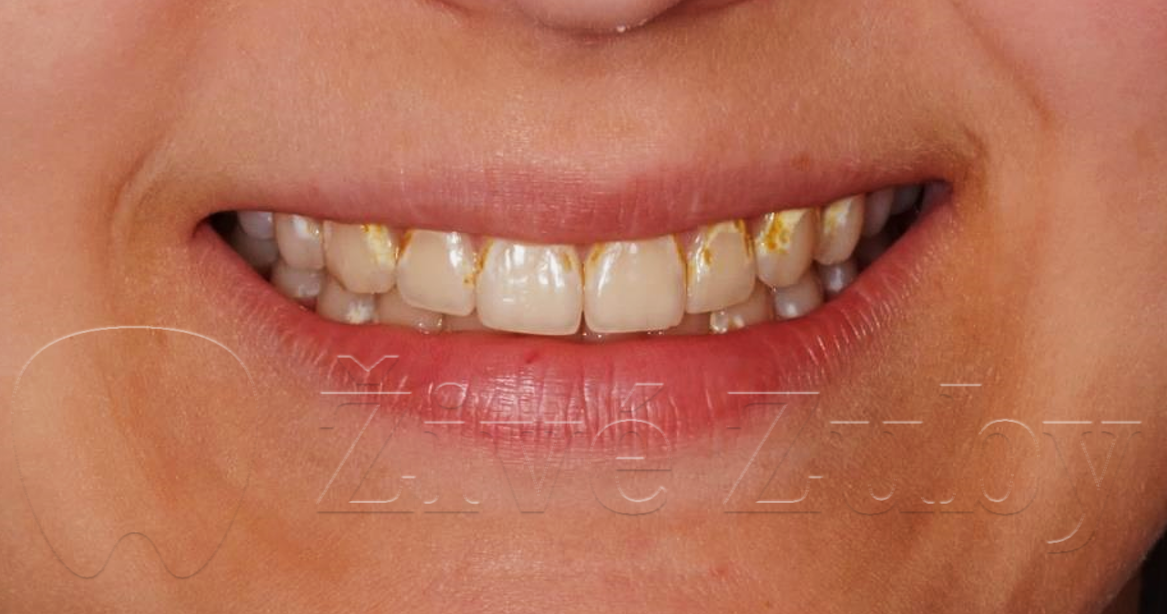

Mikroabraze a Infiltrace skloviny

(Ošetření Fluorózy a podobných lézí, demineralizaci skloviny, …)

Výchozí stav  ——- Kontrola po 2 letech